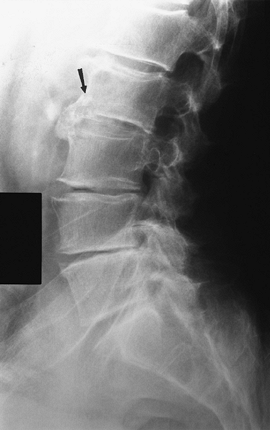

|

FIGURE 3-38 Flexion (A) and extension (B)

radiographs demonstrating anterior subluxation of L5 on S1. The degree of subluxation is determined by dividing the lower vertebral endplate into four equal segments. Subluxation is graded 1 to 4. In this case, it is Grade 1 and reduces slightly with extension. |